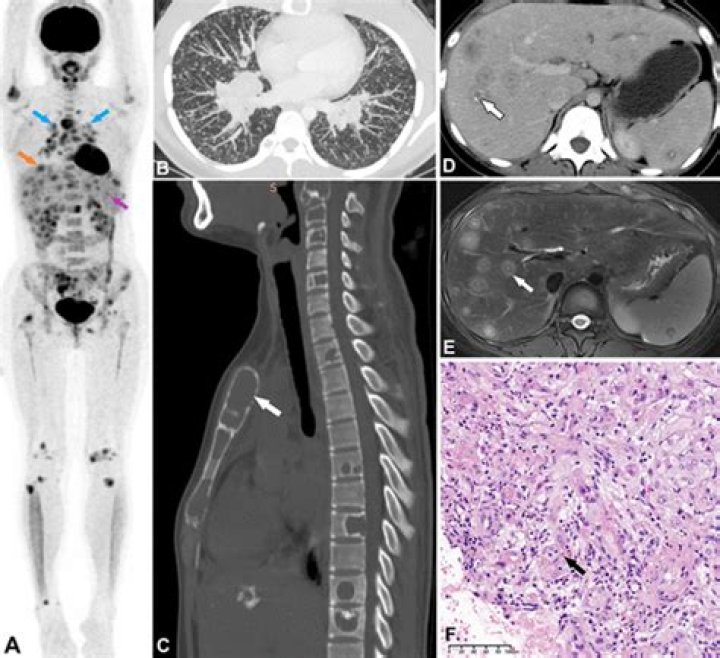

Which lung CT findings are characteristic of pulmonary epithelioid hemangioendothelioma?

Conclusions: Multiple small nodules pattern was the most common findings of pulmonary epithelioid hemangioendothelioma. Patients with pulmonary epithelioid hemangioendothelioma have good prognosis. Keywords: CT; clinical course; epithelioid hemangioendothelioma; lung.